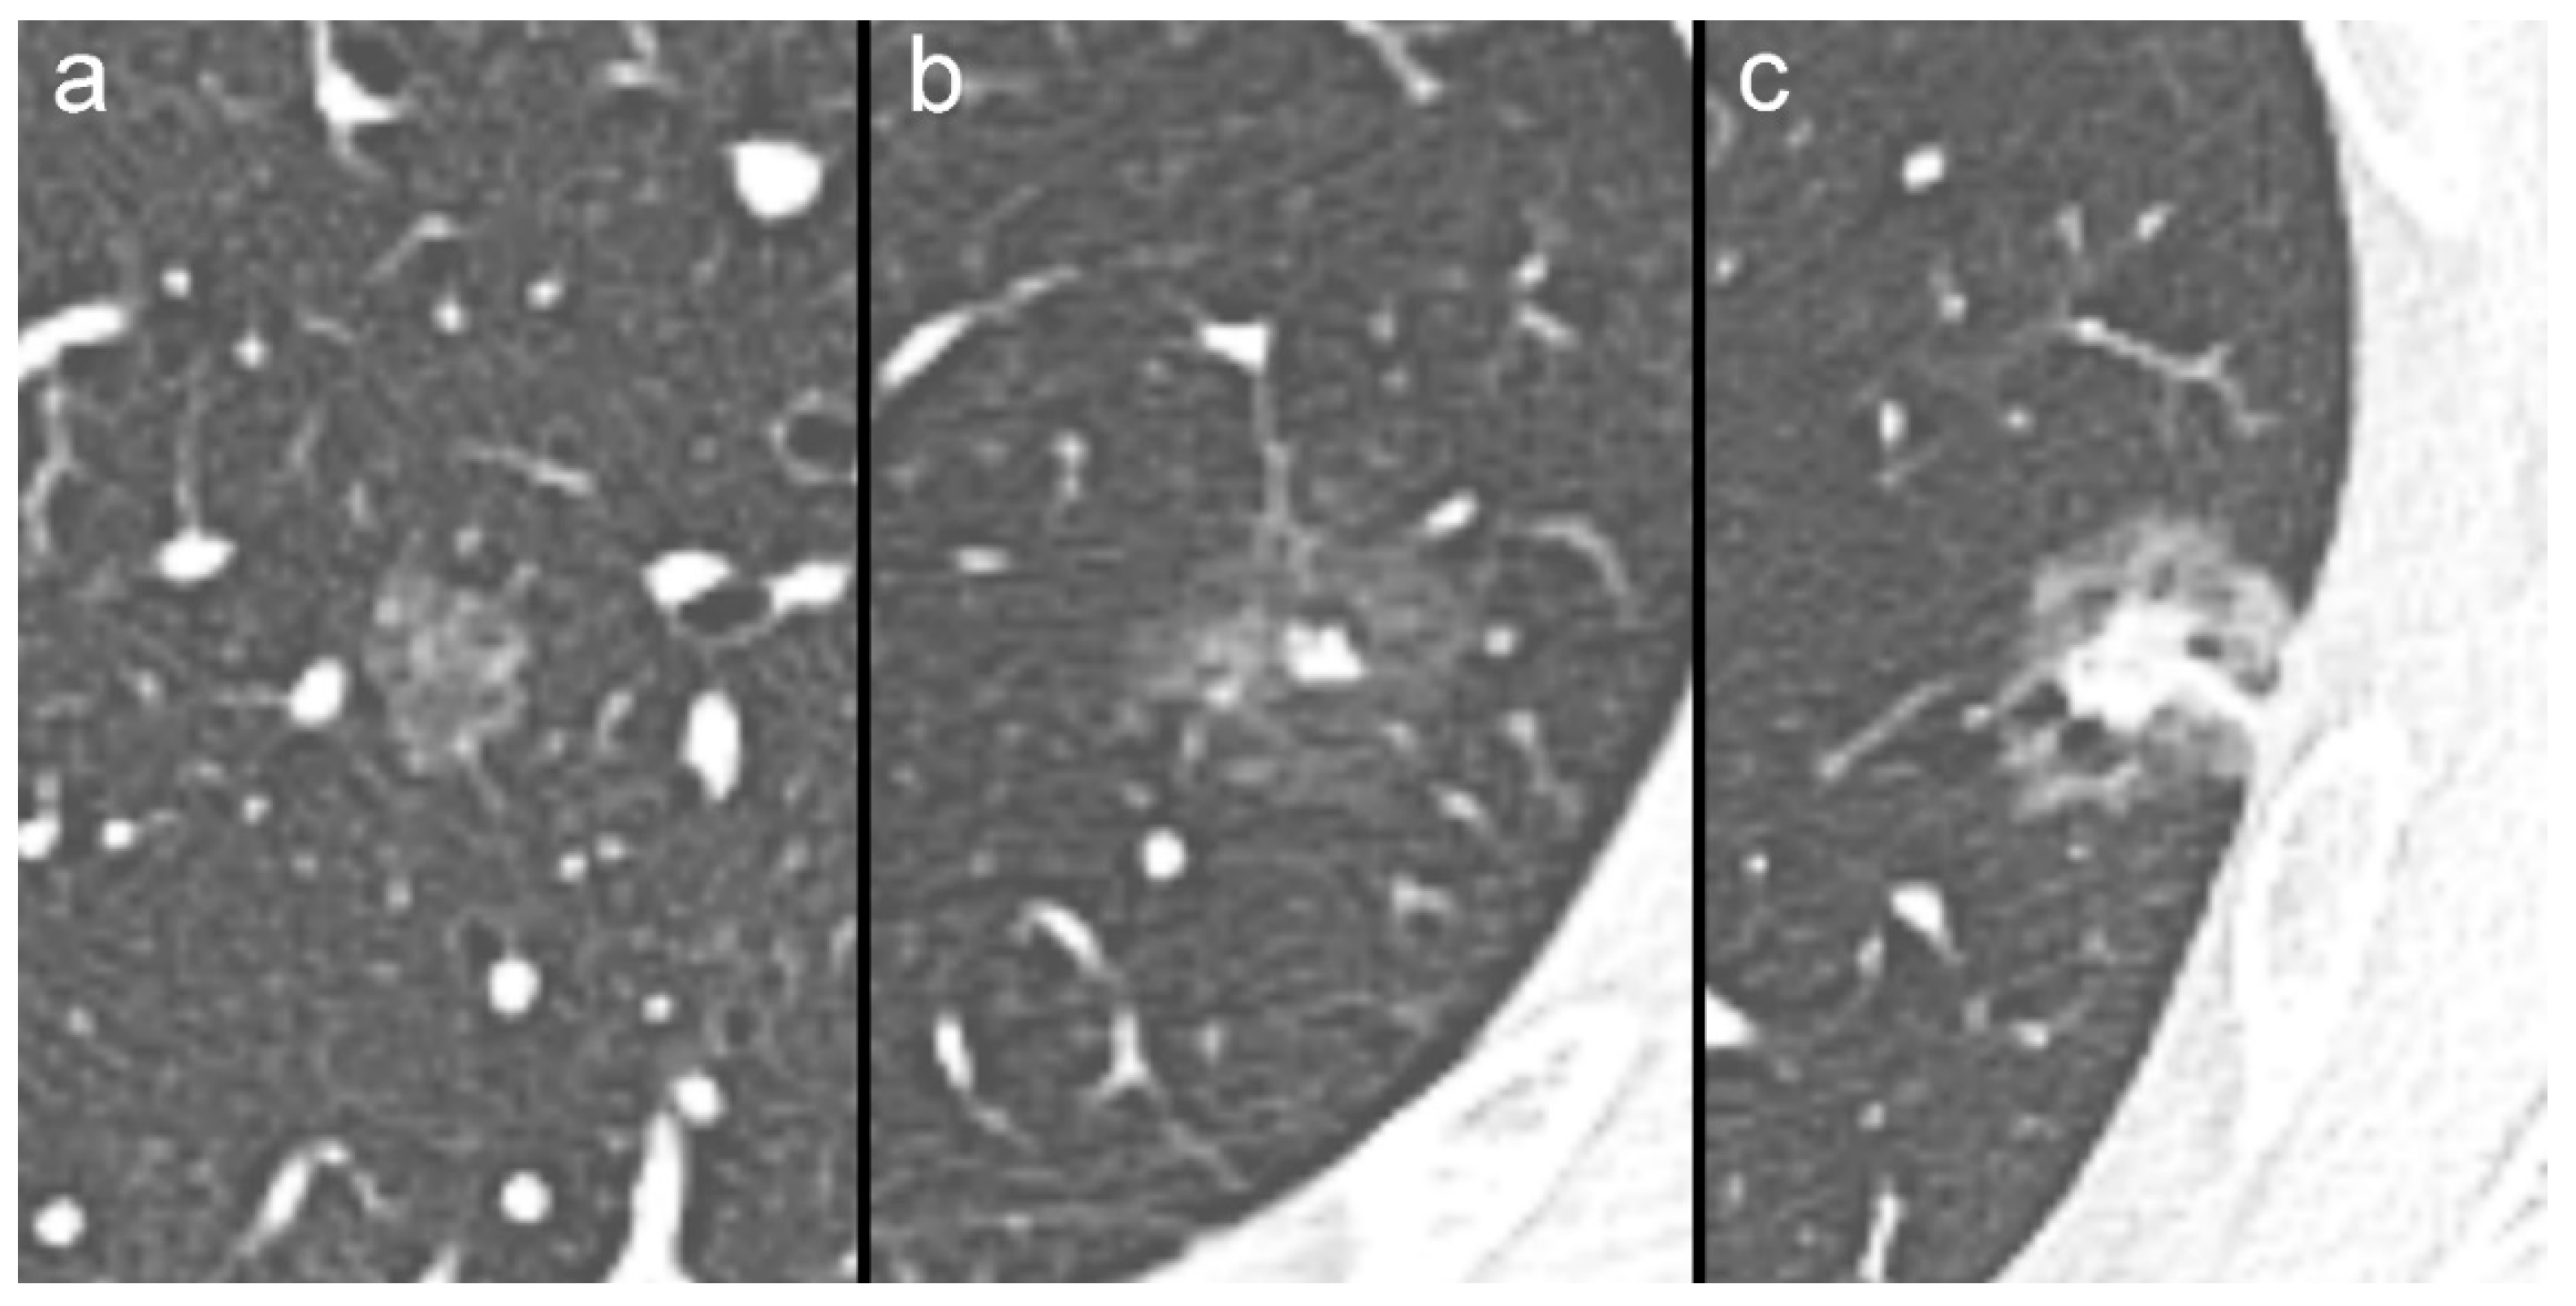

- Borghesi, A.; Michelini, S.; Bertagna, F.; Scrimieri, A.; Pezzotti, S.; Maroldi, R. Hilly or mountainous surface: A new CT feature to predict the behavior of pure ground glass nodules? Eur. J. Radiol. Open 2018, 5, 177–182. [Google Scholar] [CrossRef]